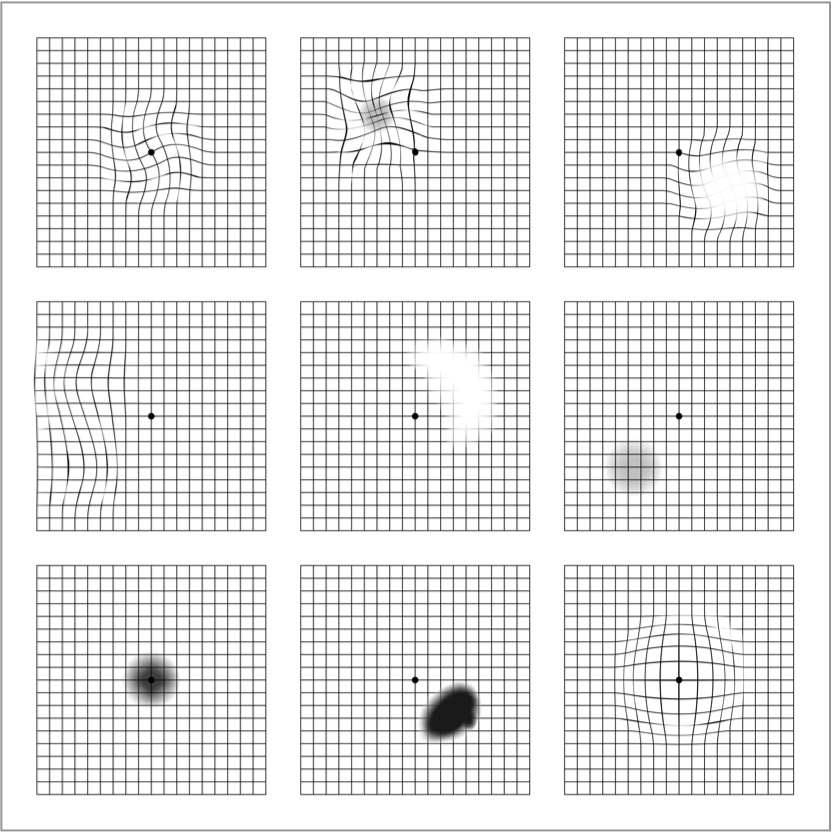

Der Amsler-Gitter-Test ist ein wichtiges1 und einfach anzuwendendes Instrument zur Selbstkontrolle, mit dem Sie Veränderungen Ihres Sehvermögens frühzeitig erkennen können. Solche Veränderungen können z. B. in Form von Verzerrungen (gerade Linien erscheinen wellenförmig) sowie verschwommenen oder dunklen Flecken auftreten.

Der Amsler-Gitter-Test eignet sich jedoch nicht als Grundlage für die Diagnose und ist kein Ersatz für regelmäßige Augenuntersuchungen. Die AMD kann ausschließlich durch eine Augenuntersuchung, einschließlich einer Untersuchung der Makula, durch einen Augenarzt diagnostiziert werden. Wird eine Veränderung des Sehvermögens anhand des Amsler-Gitter-Tests festgestellt, kann dies auch ein Anzeichen für eine andere Augenkrankheit als die AMD sein.